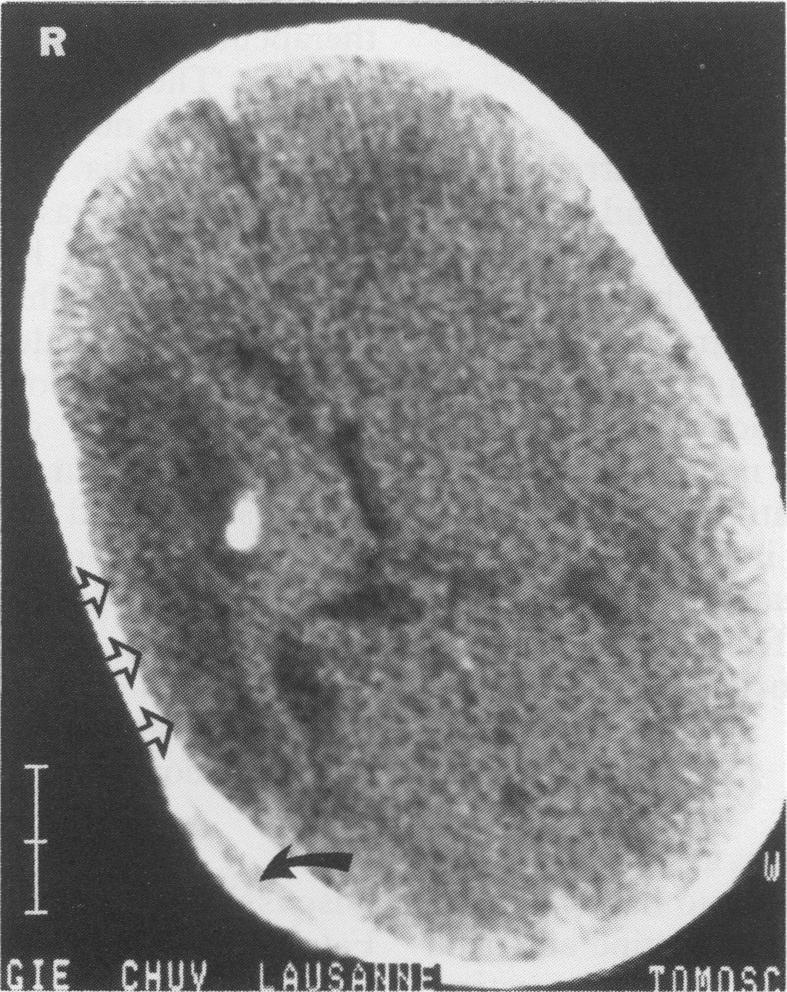

The case of a neonate who presented with symptoms of upper limb ischemia related to spontaneous multiple arterial and venous thromboses that were demonstrated by colour Doppler sonography and digital subtracted angiography is reported. The presentation of limb ischaemia at birth may be the warning sign of simultaneous cerebral infarction.

报告了一例新生儿病例,该患儿出现与自发性多发性动静脉血栓形成相关的上肢缺血症状,彩色多普勒超声和数字减影血管造影证实了这些血栓。出生时出现肢体缺血可能是同时发生脑梗死的警示信号。